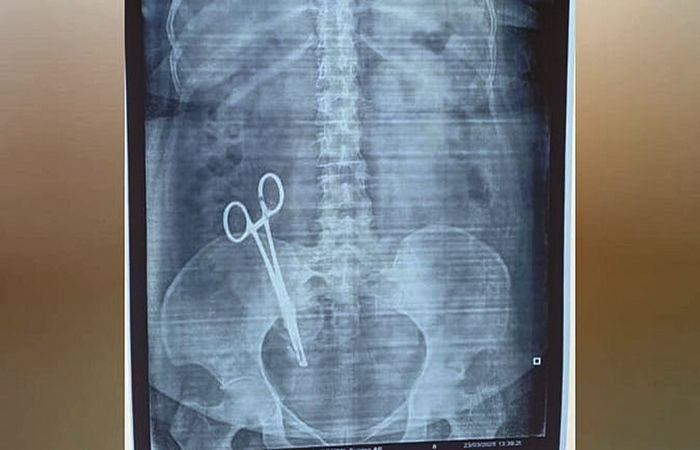

ઈન્દિરાનગર સેકટર સીની ઘટનામાં અરવિંદ કુમાર પાંડેએ ફરિયાદ કરી છે કે, તેમની પત્ની સંધ્યા 2008માં ગર્ભવતી હતી. તેને ઈન્દિરાનગરની પ્રાઈવેટ હોસ્પિટલમાં દાખલ કરવામાં આવી હતી. જ્યાં, તેણે બાળકને જન્મ આપ્યો હતો. છેલ્લા કેટલાક દિવસથી પેટમાં દુખાવો થતા તેનો એક્સ-રેકરાવવામાં આવ્યો હતો. રિપોર્ટ પરથી તેમના પેટમાં કાતર કરી ગઈ હોવાની વાતનો ઘટસ્ફોટ થયો હતો.